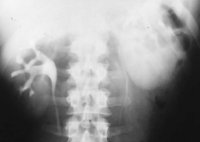

Beispielhaft die Darstellung eines ausgedehnten Nierenabszesses in Sonographie, CT und AUR (Abbildung 6).

Die Nierenfreilegung und Abszessdrainage bzw. der postoperative Krankheitsverlauf im obigen Fall (s. Abbildung 6) sind in den Abbildungen dargestellt (Abbildung 9,10).